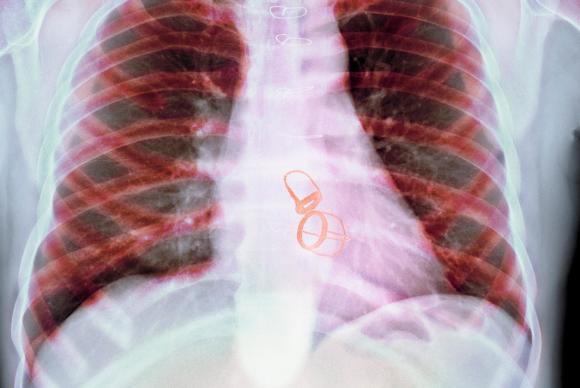

6. Treatment for Aortic Stenosis

If you have mild aortic stenosis, your doctor may just watch your condition closely. If your aortic stenosis gets worse, you may need to restrict your activities and take medicine to increase blood flow from your heart. If you have severe aortic stenosis, you may need surgery to replace the faulty valve. Without surgery, your chances of surviving for more than two years are just 50%.